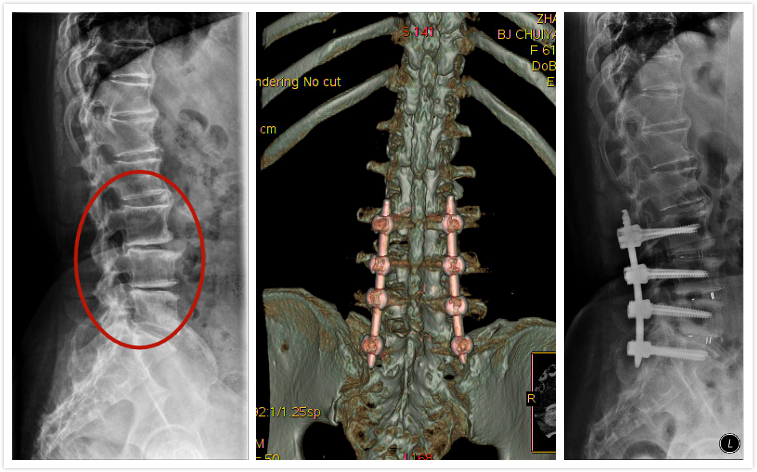

为了确保手术安全,骨四科主任姜树东带领团队,为张阿姨量身定制手术方案,并请麻醉科、内分泌科、心内科专家前来,进行联合会诊。传统上腰椎侧弯加上三个节段狭窄需要开刀手术治疗,但是根据张阿姨复杂的基础病和腰椎病情,姜树东及其团队决定为张阿姨实施“微创小切口减压融合脊柱矫形固定术”进行治疗。腰椎微创手术最常见用于治疗单节段腰椎间盘突出、腰椎管狭窄或者脊柱侧凸,三个节段以上腰椎病变一般极少采用微创方法治疗。这也是医院骨科首次为患者实施腰椎侧凸伴多节段狭窄微创减压融合固定术。

1月28日,在医院新大楼四层崭新的手术室内,姜树东带领团队医生郭函、刘正为张阿姨实施了手术。在麻醉科医生保驾护航下,首先用手术机器人辅助精准腰椎定位和植入椎弓根螺钉,随后用进口超声骨刀依次为张阿姨实施L3/4、L4/5、L5/S1三个节段小切口椎管减压融合固定。张阿姨腰椎侧凸多年,椎间孔内严重增生和狭窄,紧压着神经根,如果手术中一个不慎损伤了腰椎神经根,可能导致张阿姨下肢瘫痪。但骨四科团队医生们手法娴熟,技艺精湛,经过6个多小时的共同努力,彻底解决腰椎神经压迫,腰椎侧凸也得到了纠正。因为手术选择微创术式,术后出血量仅300ml,并通过血液回收机回输到患者体内,手术取得圆满成功!张阿姨也成为了医院首例腰椎多节段腰椎侧凸合并狭窄的微创手术受益者。